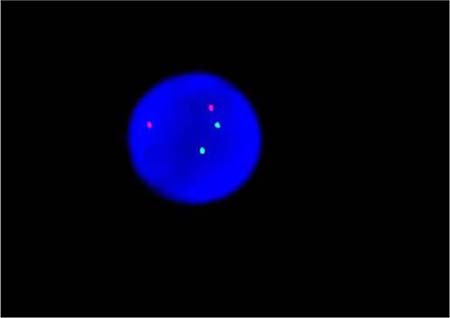

By fluorogenic quantitative PCR, centrifugation of sampled bone marrow or blood, which ACK Lysis Buffer had been added into, was conducted. Then, DNAs were extracted to be amplified. After adding samples according to the amplification system, each amplification sequence was operated in corresponding reaction conditions. The probe used for ETO genes is: Vysis LSI RUNX1/RUNXITI Dual Color, Dual Fusion Translocation Probe (Model: 08L70–020), probe map (see Figure 2). Metasystems ISIS software was applied to signal analysis. The principle of cell counting is: within a nucleus, if the distance between two signals is less than the diameter of one signal with obviously visible yellow by superposition of red and green, they can be regarded as fusion signals. Points for attention: ①. Selected cell nuclei should be complete with a clear boundary and a proper size and without fragmentation or overlapping. ②. Signals of selected cell nuclei should be bright and analysis of cells with excessively dispersed signals should be avoided. ③. By regular movement of lens (up, down, left and right), each analyzable cell should be analyzed without arbitrary omission. ④. Signal patterns of nuclei should be recorded and proportions of cells of each signal pattern to total cells should be figured out. ⑤. Detection results should be evaluated according to CUTOFF value of each positive signal pattern established by this laboratory. ⑥. After analysis of 200 cell nuclei, when the outcome is close to CUTOFF value, counting cells should be increased to 500. The normal ETO diagram (see Figure 3) and the ETO fusion diagram (see Figure 4) by fluorogenic quantitative PCR.

Figure 3: The normal ETO diagram of PCR testing.